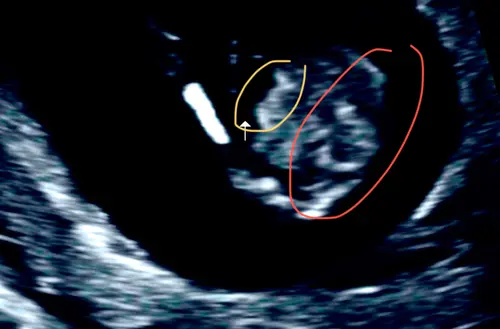

Ik bedoelde dit; het oranje is het halve rondje wat ik bedoelde ( had het idee dat dit van bovenaf de heupen/ bekken zouden zijn?)

En het gele als je inzoomt zie je duidelijk de streepjes

Dit was bij mij met 20 weken, nou zie jij het😂😂😂t was maar goed dat ze het op de achterkant geschreven had